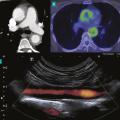

L’échographie-Doppler artérielle est un examen non invasif de première intention permettant d’explorer les artères des membres et les troncs supra-aortiques.15 Elle peut mettre en évidence un épaississement circonférentiel et homogène de la paroi artérielle, une sténose artérielle et son éventuel retentissement hémodynamique d’aval, une occlusion artérielle ou un anévrisme (fig. 2 ).

Par rapport à l’échographie-Doppler artérielle, l’angioscanner artériel a l’avantage de pouvoir explorer la portion thoracique de l’aorte. À la phase aiguë inflammatoire, on peut observer un épaississement pariétal supérieur à 3 mm, parfois une prise de contraste pariétale qui correspond à un rehaussement homogène au temps tardif de l’injection.16

Tomographie par émission de positons au 18F-FDG

La tomographie par émission de positons au 18-flurodésoxyglucose (TEP 18F-FDG) a un intérêt dans le diagnostic de la maladie, notamment dans la phase active, afin d’affirmer le caractère inflammatoire d’une aortite et la localisation précise des segments atteints, notamment chez des patients porteurs d’une forme clinique fruste. La fréquence de l’atteinte artérielle en TEP oscille entre 35 et 60 % des patients selon les études.16

Dans le suivi, elle constitue également un argument supplémentaire à l’évaluation de l’activité de la maladie en cas de positivité, toujours à confronter à l’évaluation clinique et biologique du patient.